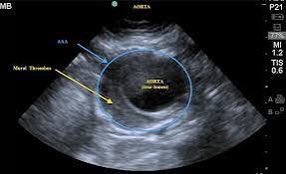

@Janburji1

A.N Moh’d, ☢️🩺

5 days

A case of Abdominal Aortic Aneurysm: Ultrasound This ultrasound image demonstrates a markedly dilated abdominal aorta, consistent with an abdominal aortic aneurysm (AAA). Ultrasound is the first-line imaging modality for AAA detection and screening due to its high sensitivity,…

4

18

102